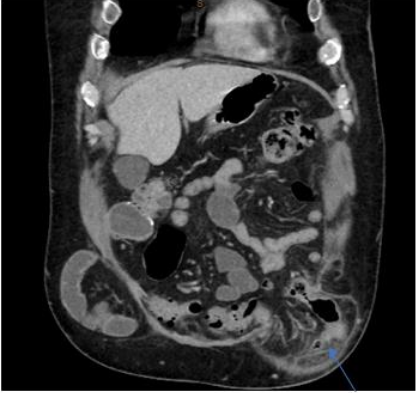

Laboratory investigations showed a white cell count (WCC) within normal limits at 10.9x109/L and a mildly elevated CRP level at 54.9. A CT-abdomen ordered by the patient’s GP prior to presentation to ED showed sigmoid colon diverticulitis with the area of diverticulitis occurring at the efferent loop of large bowel within a large fat and bowel-containing left-sided indirect inguinal hernia without signs of acute bowel obstruction (Figure. 1).

Figure 1: Coronal view of CT-abdomen/pelvis showing incarcerated left-sided inguinal hernia